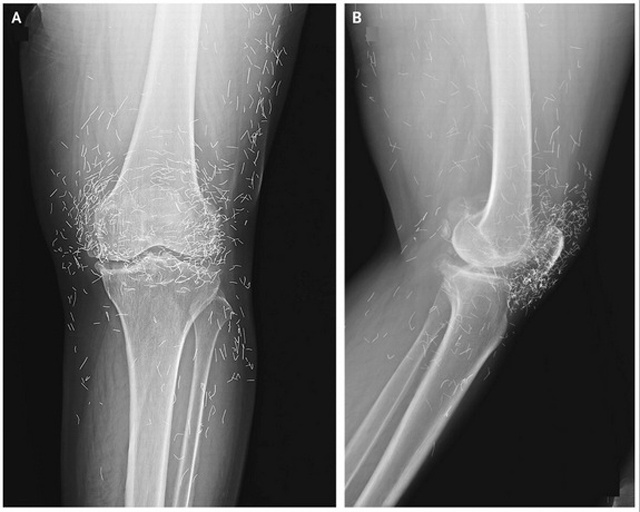

സ്‌ത്രീയുടെ കാല്‍മുട്ടില്‍ നൂറുകണക്കിന് സ്വര്‍ണ സൂചികള്‍ കണ്ടെത്തി

സിയൂള്‍: സന്ധിവേദനയെത്തുടര്‍ന്ന് ആശുപത്രിയിലെത്തിയ സ്ത്രീയുടെ കാല്‍മുട്ട് പരിശോധിച്ചപ്പോള്‍ കണ്ടെത്തിയത് നൂറുകണക്കിനു സ്വര്‍ണസൂചികള്‍!അറുപത്തഞ്ചു വയസുള്ള സ്ത്രീ തുടര്‍ച്ചയായ ചികിത്സയിലും വേദന മാറിയില്ലെന്നു പരാതിപ്പെട്ടപ്പോള്‍ നടത്തിയ എക്‌സ്‌റേ പരിശോ... [Read More]